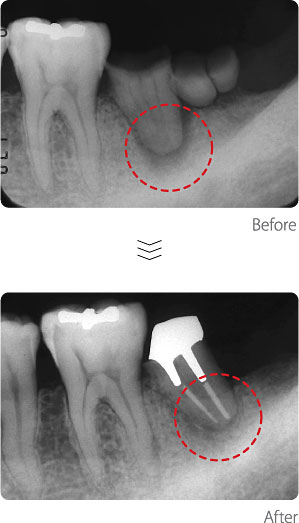

根管治療〈Case2〉

Case1と同様に、歯根の周囲の骨が、根の中からの細菌に侵され、溶けてきています。根管治療後、細菌がいなくなり、骨が再生しています。右端の一番奥の小さな歯(親知らず)は、むし歯が極めて進行し、歯根がほとんど溶けてなくなってしまう手遅れの状態となっていたために、残念ながら抜歯となりました。